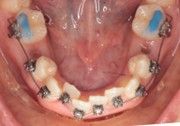

The IOS Mini Cinch Back Plier demonstrated superior control and a significantly reduced risk of bracket debonding and wire deformation compared to the regular Hammerhead plier from a different brand. Wire bends achieved with the IOS Mini Cinch Back Plier maintained integrity even under high-torque activation. The following images illustrate key differences in bend quality, wire distortion, and proximity to the bracket between the IOS Mini Cinch Back Plier and the conventional Hammerhead plier.